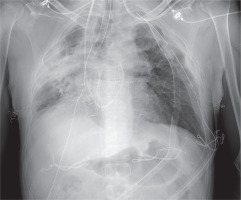

We present a case of a 43-year-old man with respiratory failure in the course of chronic dysfunction of lungs. The patient had been diagnosed with many chronic conditions, such us post-transplantation renal insufficiency, post-transplantation diabetes (PTD), exocrine pancreatic insufficiency, and osteopenia. In 2014, 4 years prior to the described events, the patient underwent lung transplantation due to the advancement and progression of cystic fibrosis. He was operated on in a different European lung transplantation center. The early and late post-transplantation periods were complicated by chronic infection with Pseudomonas aeruginosa and Pneumocystis jiroveci in 2015 and 2016. From March 2016, there was a gradual deterioration of breathing. The biopsy revealed chronic graft rejection with the BOS 1 subtype (forced expiratory volume in 1 second (FEV1) 80%); therefore, steroid therapy was administered. Six months later, the patient’s condition deteriorated, with a significant impairment of FEV1, requiring antithymocyte globulin ATG and further extracorporeal photopheresis treatment. In 2017 the patient developed oxygen-dependent respiratory failure with a rapidly decreasing FEV1 from 60% to 40%. As a consequence, the patient was successfully qualified for lung retransplantation. In October 2018, the patient underwent retransplantation of the left lung at our center. Veno-arterial extracorporeal membrane oxygenation (ECMO) with peripheral cannulation was commenced owing to the expected chest adhesions. After surgical exposure via a clamshell incision through the previous scar, the anatomical structures were difficult to identify. The preparation was started from the left lung. Because of the existing difficult anatomical conditions and thus the prolonged ischemic time for the first lung (11 hours), the transplantation of the second lung was cancelled (Figure 1). The patient was then transferred to the intensive care unit (ICU) and extubated on the third postoperative day. Due to postoperative renal failure on the first day after retransplantation, the patient required renal replacement therapy. On the 10th postoperative day, it was decided to perform pneumonectomy of the right lung, due to increasing dyspnoea and significant pulmonary leakage in the previous graft. During ICU stay, on the 17th day after retransplantation, because of the persistent postoperative bleeding into the post-resection cavity, rethoracotomy with a successful hemostatic effect was performed. The patient was discharged home on the 66th postoperative day (Figure 2). In a two-month follow-up, the patient was in a good overall condition with progressive improvement of respiratory function and FEV1.